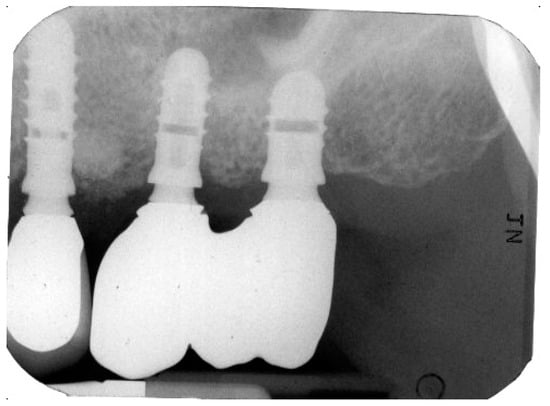

Figure 2 and Figure 3 illustrate the case conclusion, featuring an X-ray of the prosthetic rehabilitation after the extraction of the implant and neighboring teeth, along with an image of the completed prosthesis.

Figure 2.

X-ray after the implant retrieval and rehabilitation restoration.